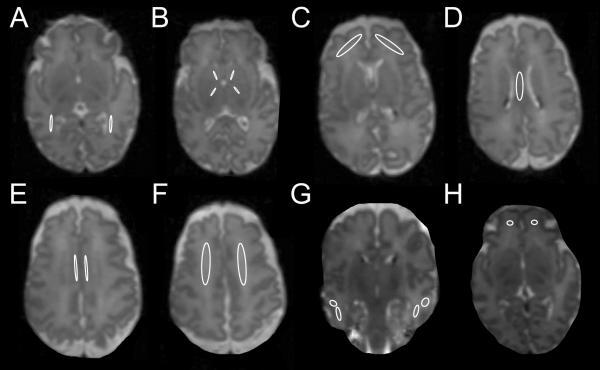

Serial diffusion tensor magnetic resonance imaging data were obtained from very preterm infants (N = 78) born <30 wk gestation imaged up to four times from 26-42 wk postmenstrual age. Slopes were calculated for fractional anisotropy (FA) and mean diffusivity (MD) within regions of interest for infants with ≥2 scans (N = 50). Sixty-five children underwent neurodevelopmental testing at 2 y of age.

FA slope for the posterior limb of the internal capsule was greater than other regions. The anterior limb of the internal capsule (ALIC), corpus callosum, and optic radiations demonstrated greater FA slope with increasing gestational age. Infants with patent ductus arteriosus had lower FA slope in the ALIC. MD slope was lower with prolonged ventilation or lack of antenatal steroids. At 2 y of age, lower motor scores were associated with lower FA in the left but higher FA in the right inferior temporal lobe at term-equivalent age. Better social-emotional competence was related to lower FA in the left cingulum bundle.